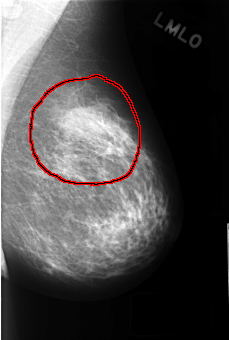

C_0435_1.LEFT_MLO

LEFT_MLO LINES 4408 PIXELS_PER_LINE 2968 BITS_PER_PIXEL 12 RESOLUTION 50 OVERLAY

FILE: C_0435_1.LEFT_MLO.OVERLAY

TOTAL_ABNORMALITIES 1

ABNORMALITY 1

LESION_TYPE MASS SHAPE ASYMMETRIC_BREAST_TISSUE MARGINS N/A

ASSESSMENT 3

SUBTLETY 5

PATHOLOGY BENIGN_WITHOUT_CALLBACK

TOTAL_OUTLINES 1

BOUNDARY